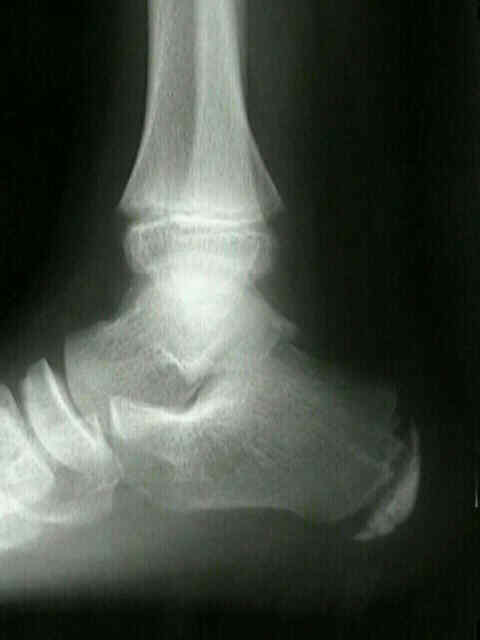

- Sever’s Disease

Sever’s Disease is the number one cause of heel pain in children. Pain is localized to the bottom and sides of the heel toward the back of the foot. Pain typically gets worse with an increase in activity and maybe made worse by individuals carrying extra weight. Apophysitis can become more chronic while growth plates are open if activity is not limited during acute phase. Sever’s Disease can have a dull achy pain or a sharp pain, the pain does not radiate or shoot normally. Unfortunately, overweight patients are predisposed to developing apophysitis

Sever’s Disease Treatment

Severe’s Disease treatment requires reduction in activity. Reduction in active on the feet activity is critical in the reduction of acute symptoms, often this can be difficult due to sports or other activities. Heel cups and gel heel cushions can help reduce the repetitive trauma and inflammation of the area around the heel.